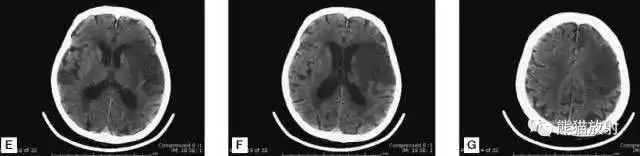

▲

左侧大脑中动脉供血区脑梗死(亚急性期):

低密度,轻度水肿

缺血性脑卒中发作2-4天时,占位效应最明显。